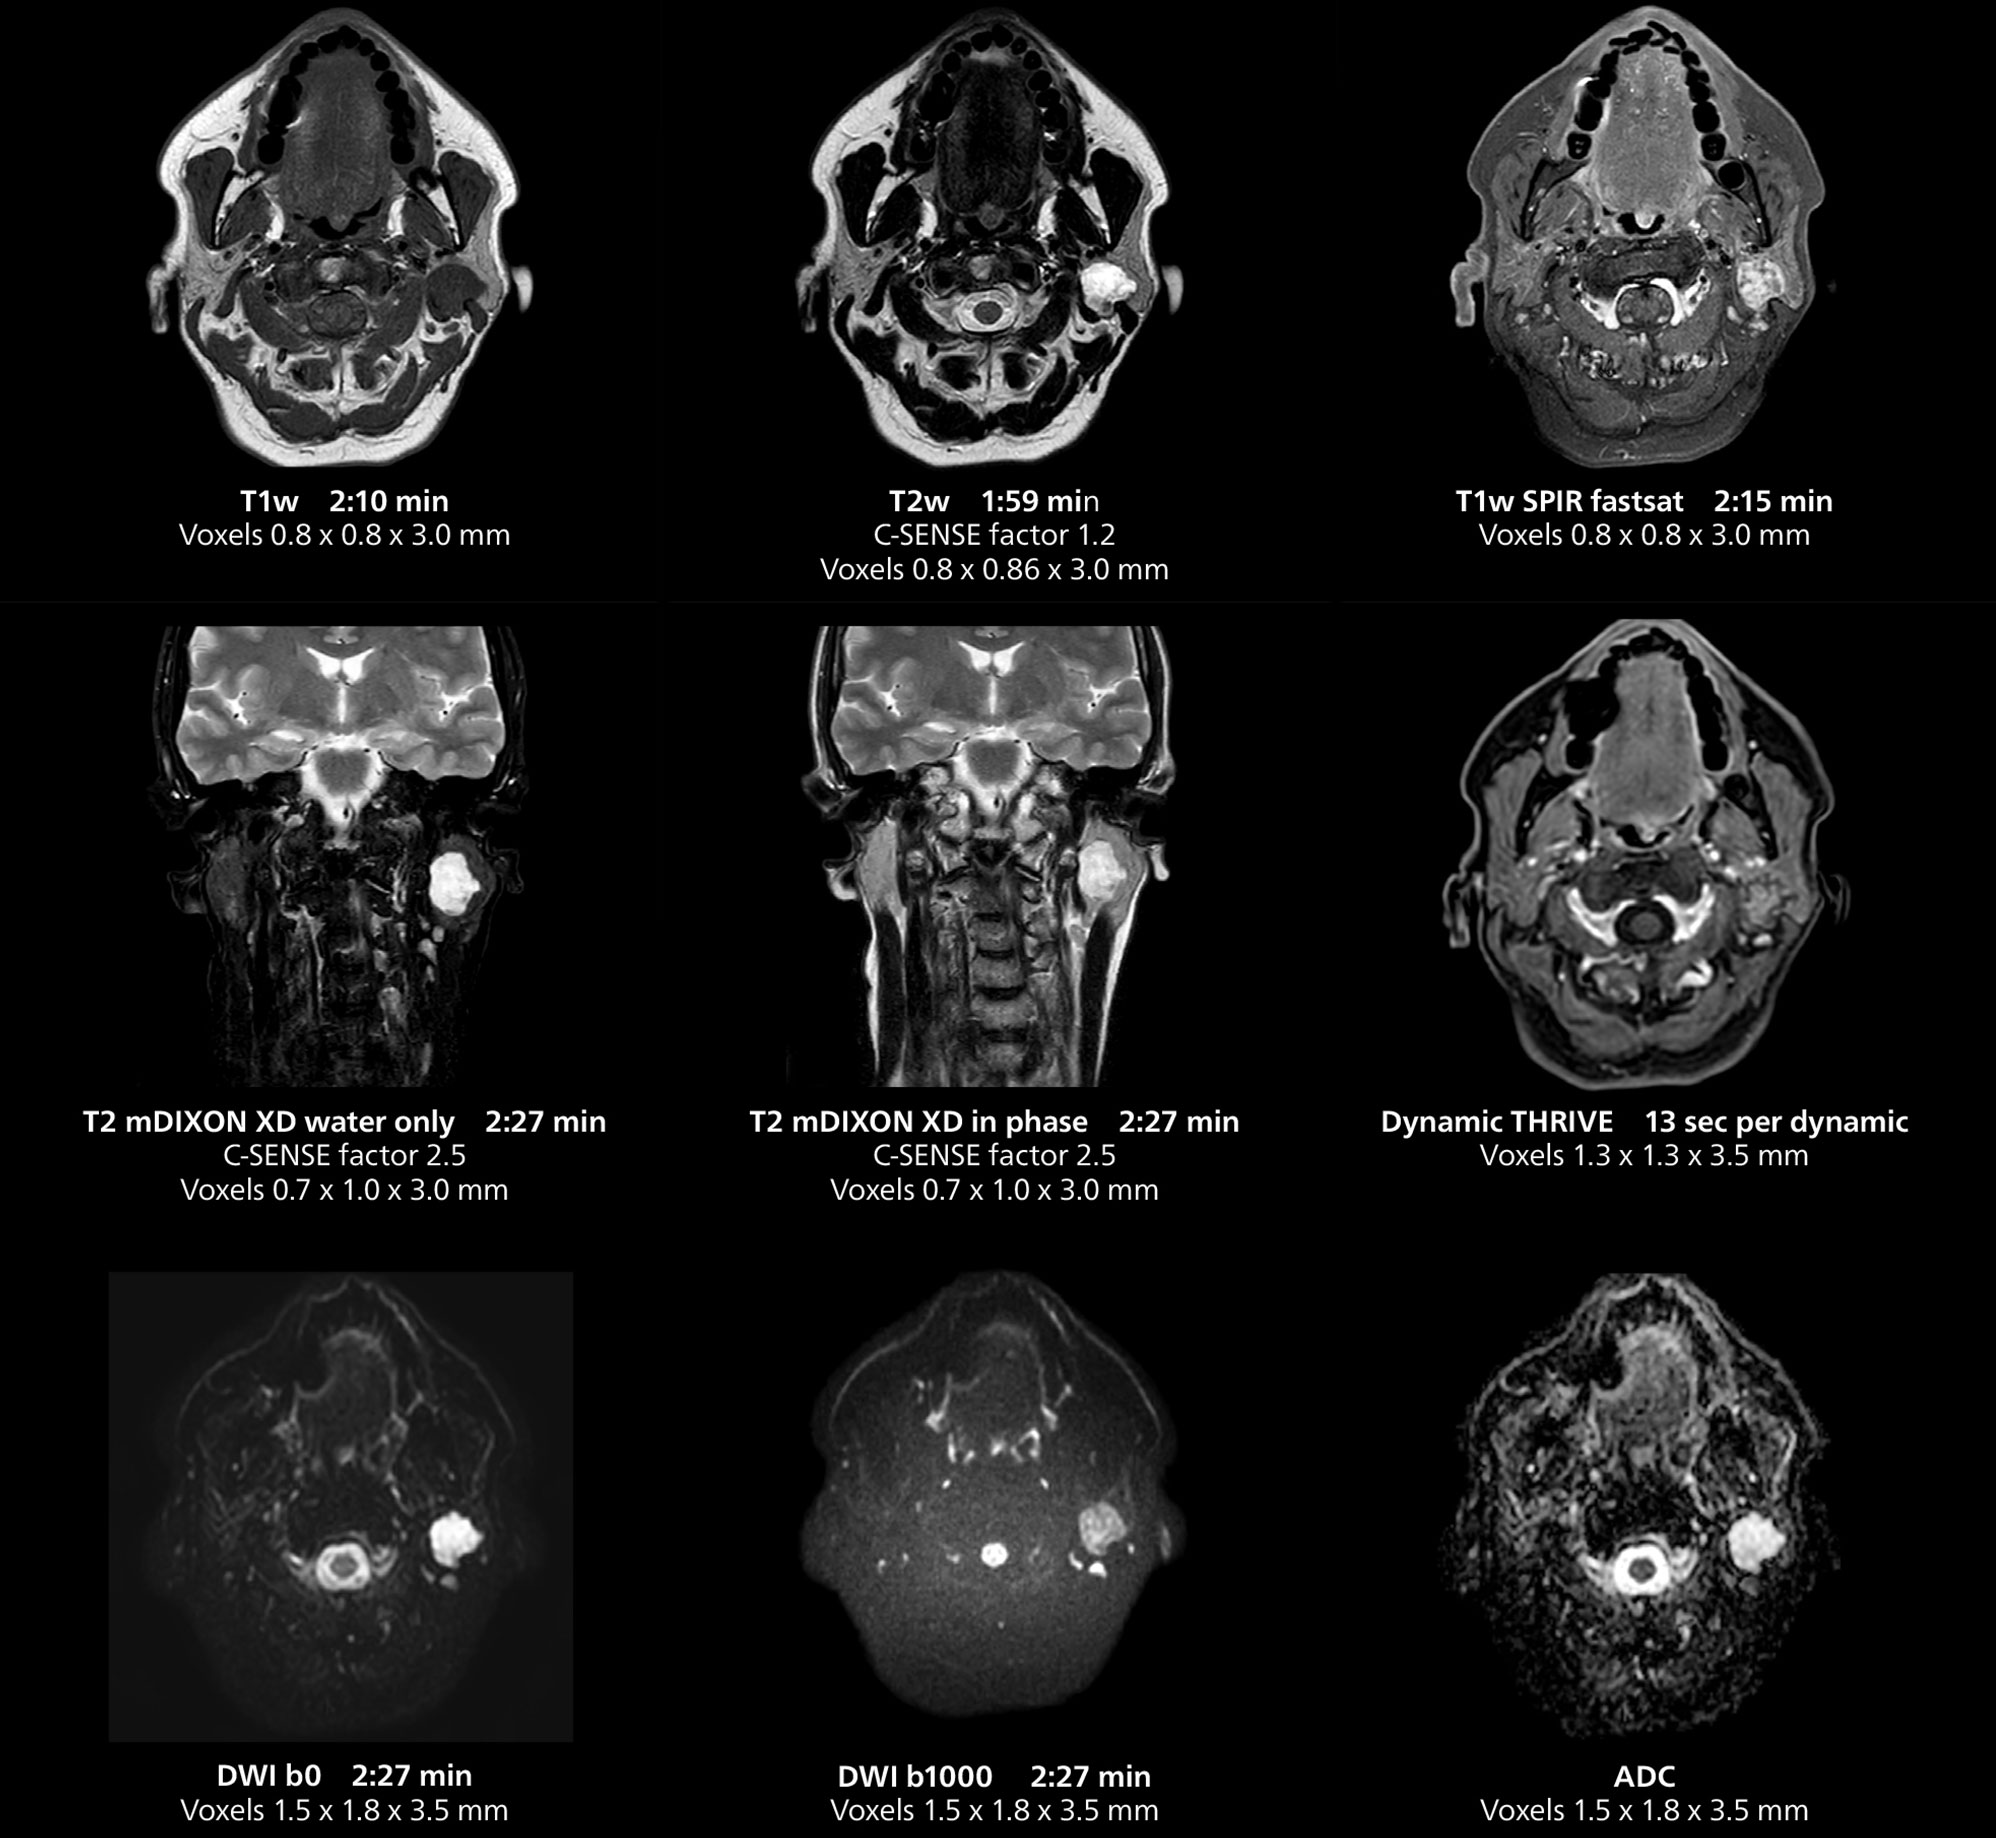

Salivary gland imaging on MR 5300

This MRI case illustrates imaging of salivary gland abnormalities with different sequences. Compressed SENSE allows to accelerate scanning while maintaining high quality. With mDIXON XD, different contrast types can be obtained from scanning one sequence.